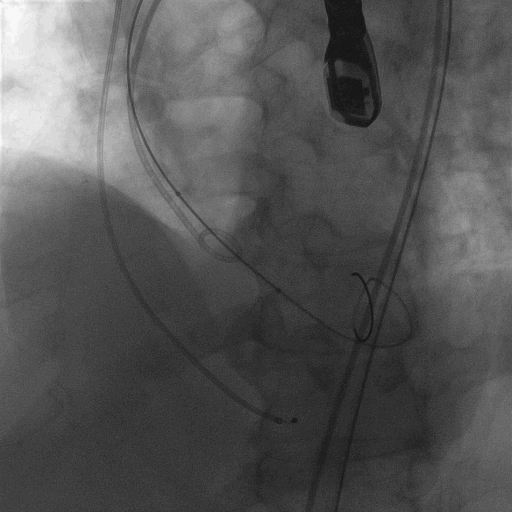

术中造影

18mm球囊预扩,有腰无漏

L23超高位释放